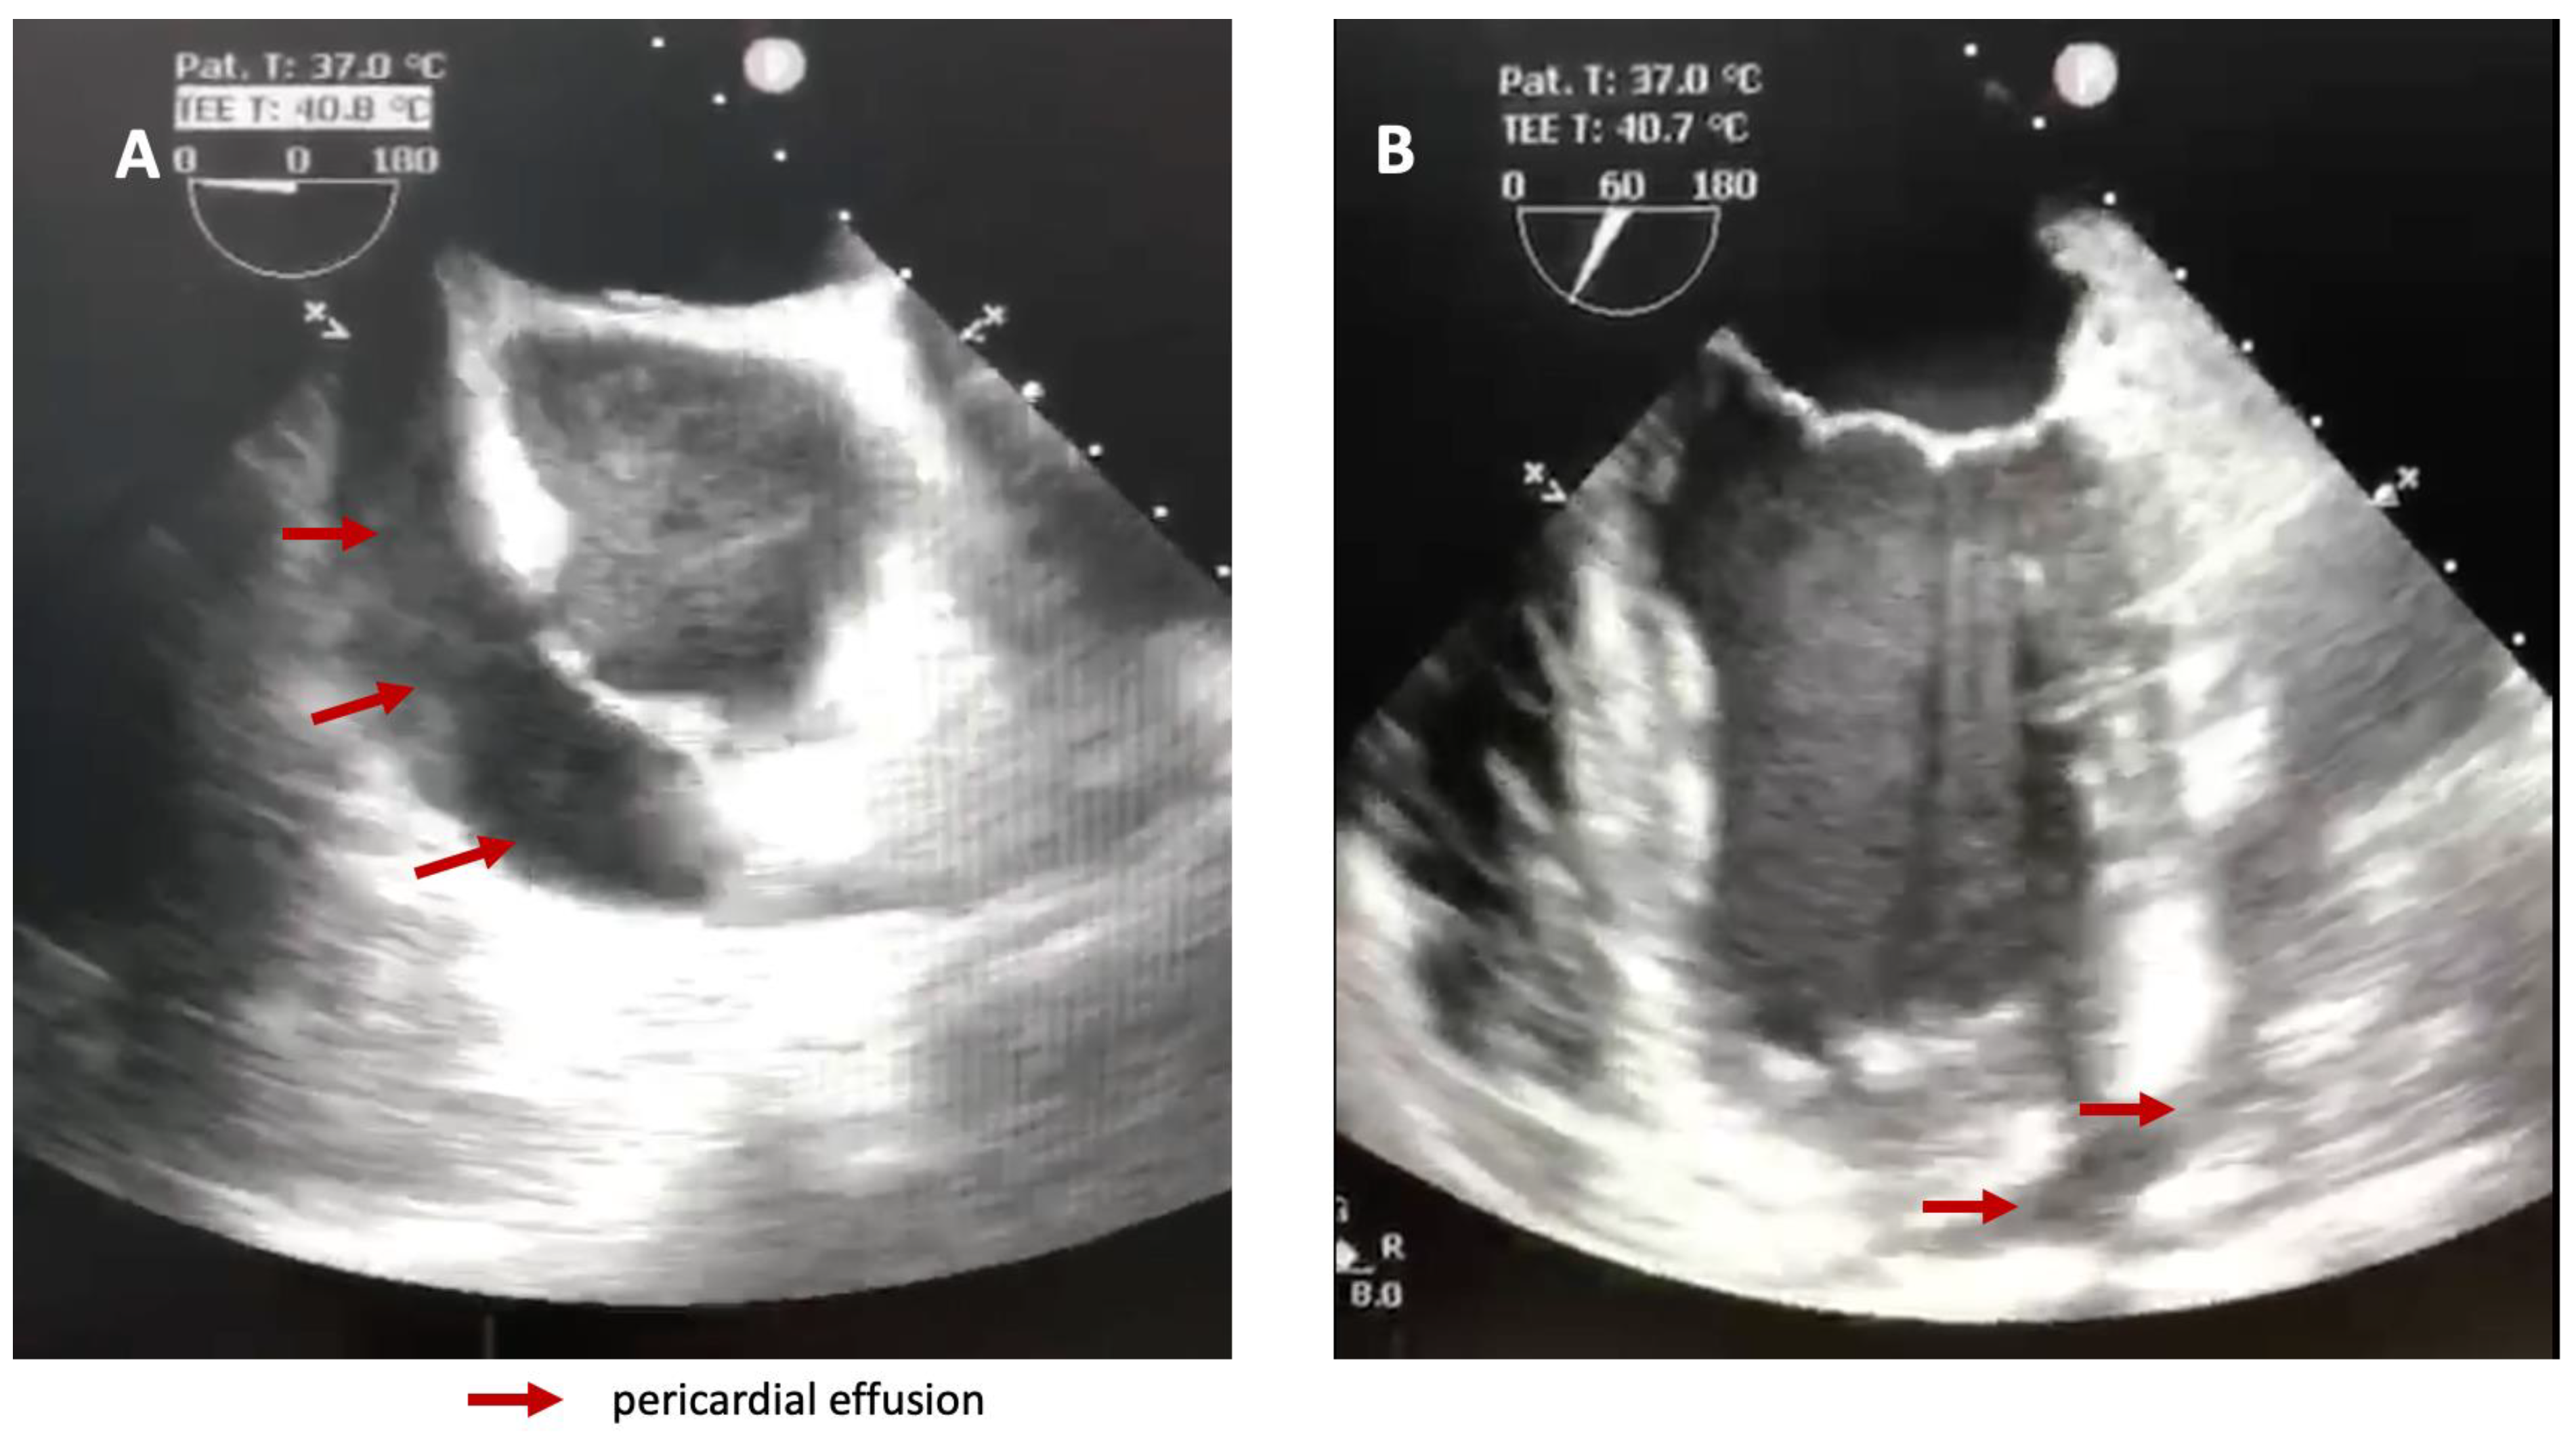

Repeated thoracic CT displayed significant circumferential pericardial effusion adjacent to the left ventricle and minimal bilateral pleural effusion (Figure 1).

Figure 1. Thoracic CT showing circumferential pericarditis.